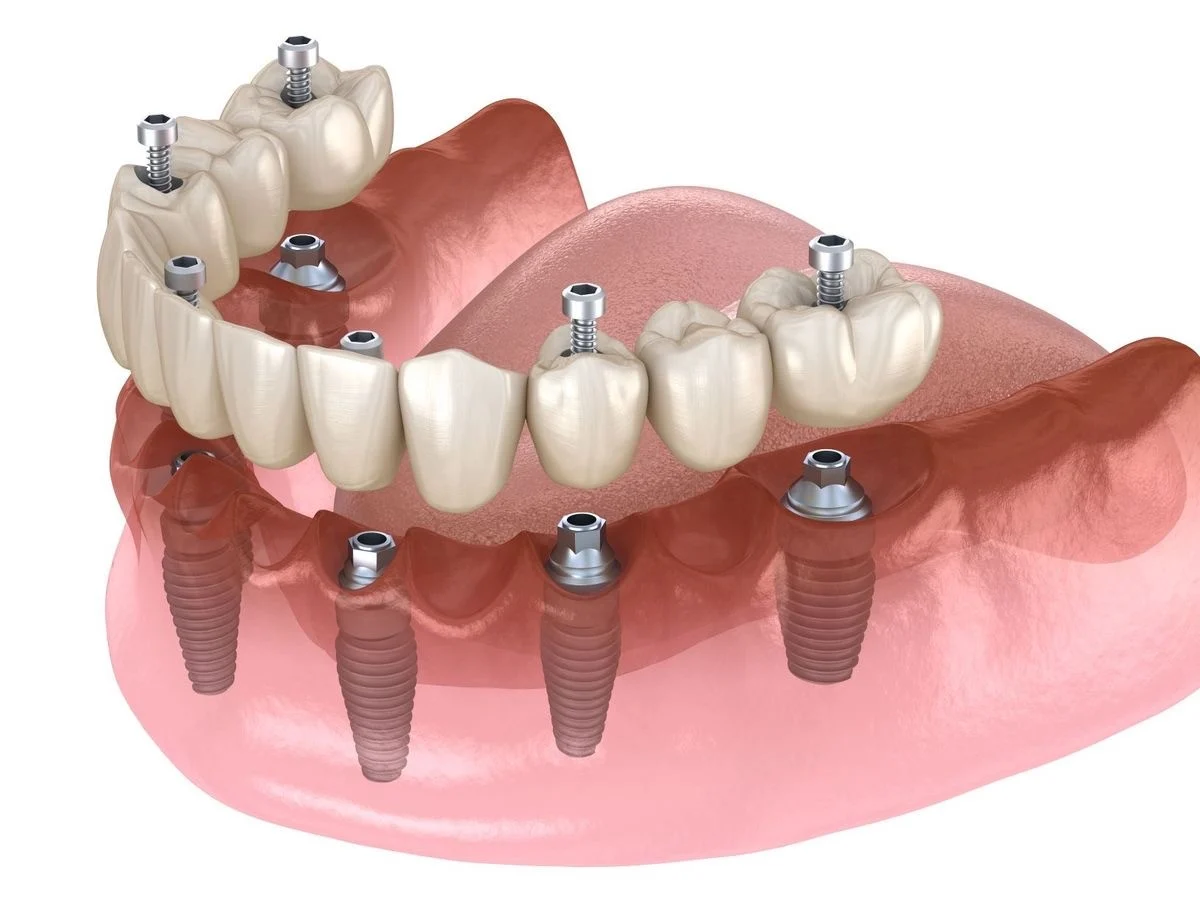

Nadoknade na implantima

Nakon ugradnje implanata, pristupa se izradi kruničnog dela nadoknade, pri čemu se u ustima ne moze zapaziti prisustvo implanta. Visokoestetski zahtevi su postignuti primenom bezmetalne keramike kojom se postize izvanredna estetika i najprirodniji izgled.

U zavisnosti od indikacija i želje pacijenta, nadoknade mogu biti izradjene od keramike koja kao osnovu ima metal ili od visokoestetske bezmetalne keramike kojom se postiže izgled najbliži prirodnom zubu.

Implanti

U savremenoj stomatologiji implanti zauzimaju važno mesto u nadoknadi izgubljenih zuba i vraćanju funkcije žvakanja. Korišćenjem najkvalitetnijih implanata u stomatologiji, stomatološka ordinacija Kocić obezbedjuje vrhunske rezultate u protetskoj rehabilitaciji usne duplje.

Uz primenu najsavremenije opreme i adekvatnih lokalnih anestetika, bezbolan rad je zagarantovan, uz optimalno vreme oporavka.